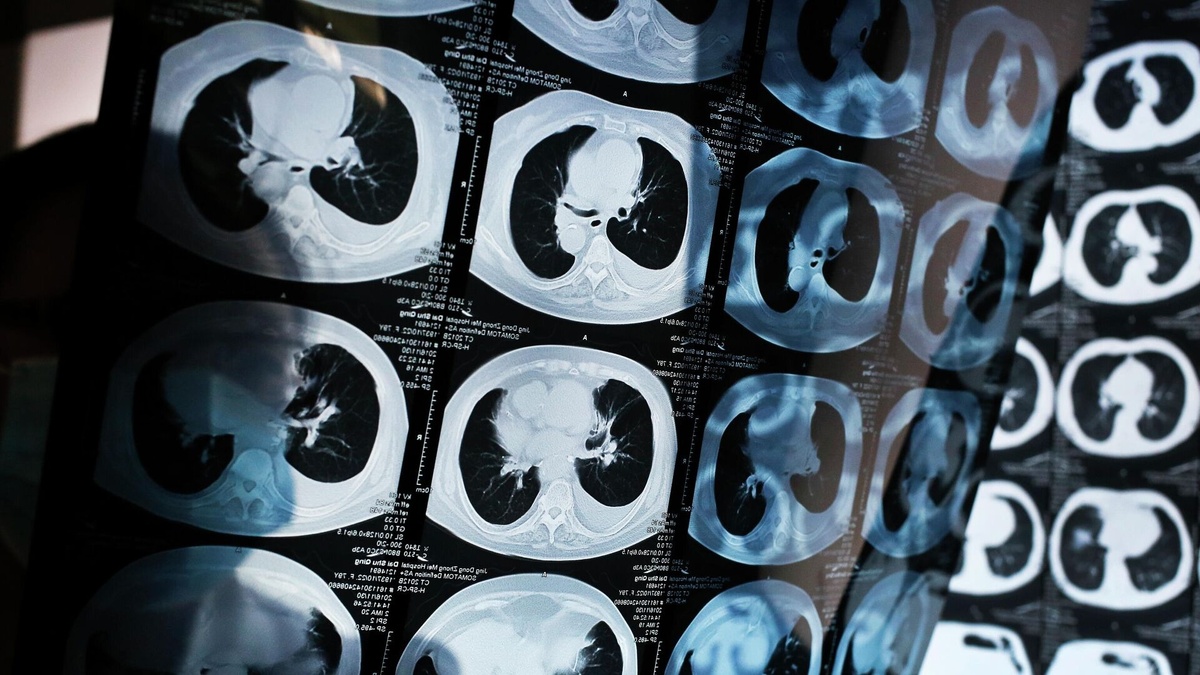

2. Биология роста опухоли. Злокачественное образование не появляется за одну ночь. От первой мутировавшей клетки до опухоли размером 1 см, которую можно обнаружить на КТ, может пройти до нескольких лет. Все это время она «молча» растет, не оказывая значительного системного влияния на организм.

3. Проходите скрининги. Это главный ответ на «немой» рак. Скрининговые программы (маммография, ПАП-тест, колоноскопия, низкодозовая КТ легких для курильщиков, ПСА) созданы именно для того, чтобы найти болезнь до появления симптомов, на той стадии, когда она излечима в большинстве случаев.